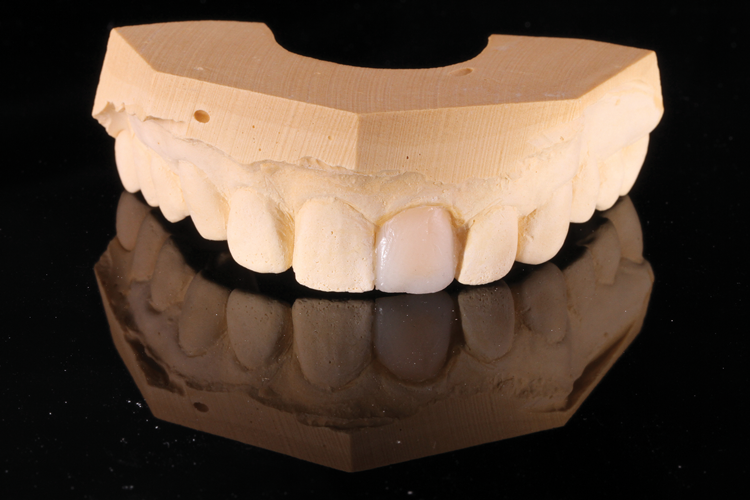

(3.) A stone model was fabricated with the tooth to be replaced still in position.

Figure 3

(4.) The tooth on the model was prepared for a traditional crown with the gingival margins ideally placed.

Figure 4

(5.) The tooth on the model was prepared for a traditional crown with the gingival margins ideally placed.

Figure 5

(6.) Using dentin opacity composite, the tooth shell was shaped directly onto the prepared tooth on the model.

Figure 6

(7.) The composite was cured, and the tooth shell was snapped off of the model. Then, the stone inside of it and the composite flash at the margins were removed.

Figure 7

(8.) The composite was cured, and the tooth shell was snapped off of the model. Then, the stone inside of it and the composite flash at the margins were removed.

Figure 8

(9.) Intaglio and facial views of the cleaned and polished composite shell, which is ready for conversion into the provisional restoration.

Figure 9

(10.) Intaglio and facial views of the cleaned and polished composite shell, which is ready for conversion into the provisional restoration.

Figure 10